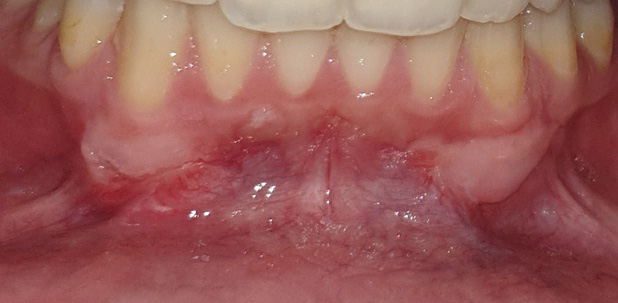

The graft was positioned in its bed and held pressed for 2 min for initial stability. At one side, the graft was stabilized using 0/5 nylon sutures (interrupted sutures to the papilla and a sling suture were placed to adapt the graft intimately to the root and periosteal bed),25 while at the other side, FGG was stabilized with the tissue adhesive (Figure 2, Figure 3, Figure 4).

As to the healing index, there were no significant differences between the 2 sites after 1 week, 2 weeks, 1 month, and 2 months. However, the healing process was completed 1 month postoperatively in the tissue adhesive group, whereas in the suture group, it lasted up to 2 months (Table 5) (Figure 5, Figure 6, Figure 7).